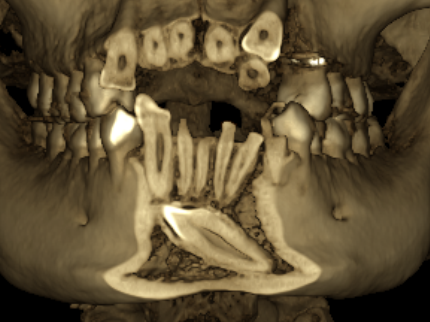

☆本院特別巨資增設 ”千萬級3D AI透視電腦斷層”,並配合“成骨膠原蛋白”施作 (上述兩項目前健保無給付),讓您遠離神經傷害、口鼻竇(炎)相通...等併發症,除健保之外,難免會有避免併發症風險的自費項目,網路上經常會有看到智齒拔完後唇麻、舌麻、口鼻竇相通等併發症,在本院嚴格自我要求下,此類併發症在本院幾乎趨近於零。

(兩條紅線中間黑色區域即為神經管)

外面拔完時常術後唇麻舌麻,本院發生趨近於零

外面拔時易斷裂於骨頭內而難以取出